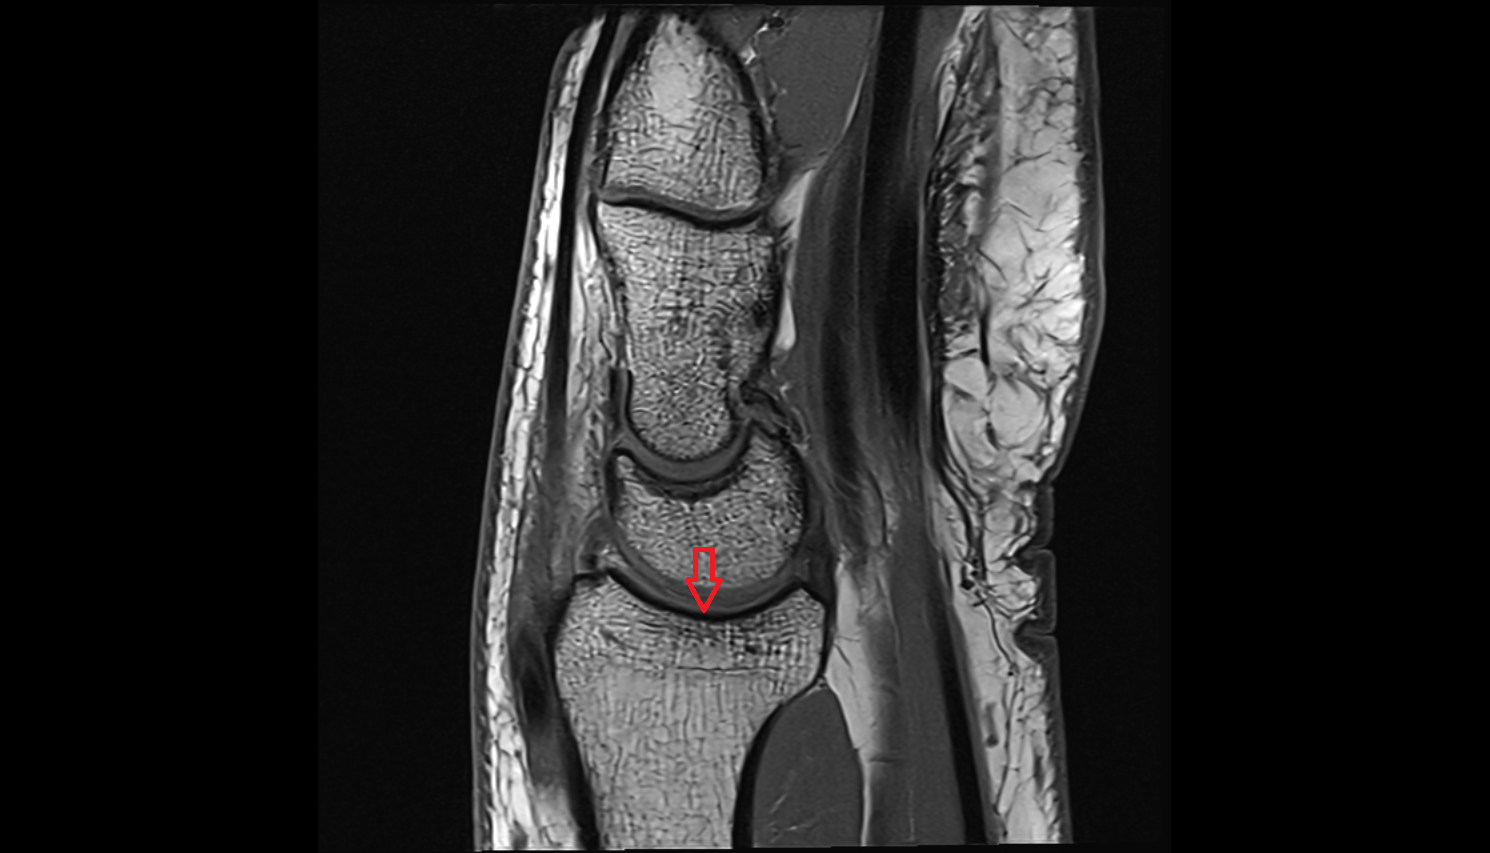

- Knee Joint